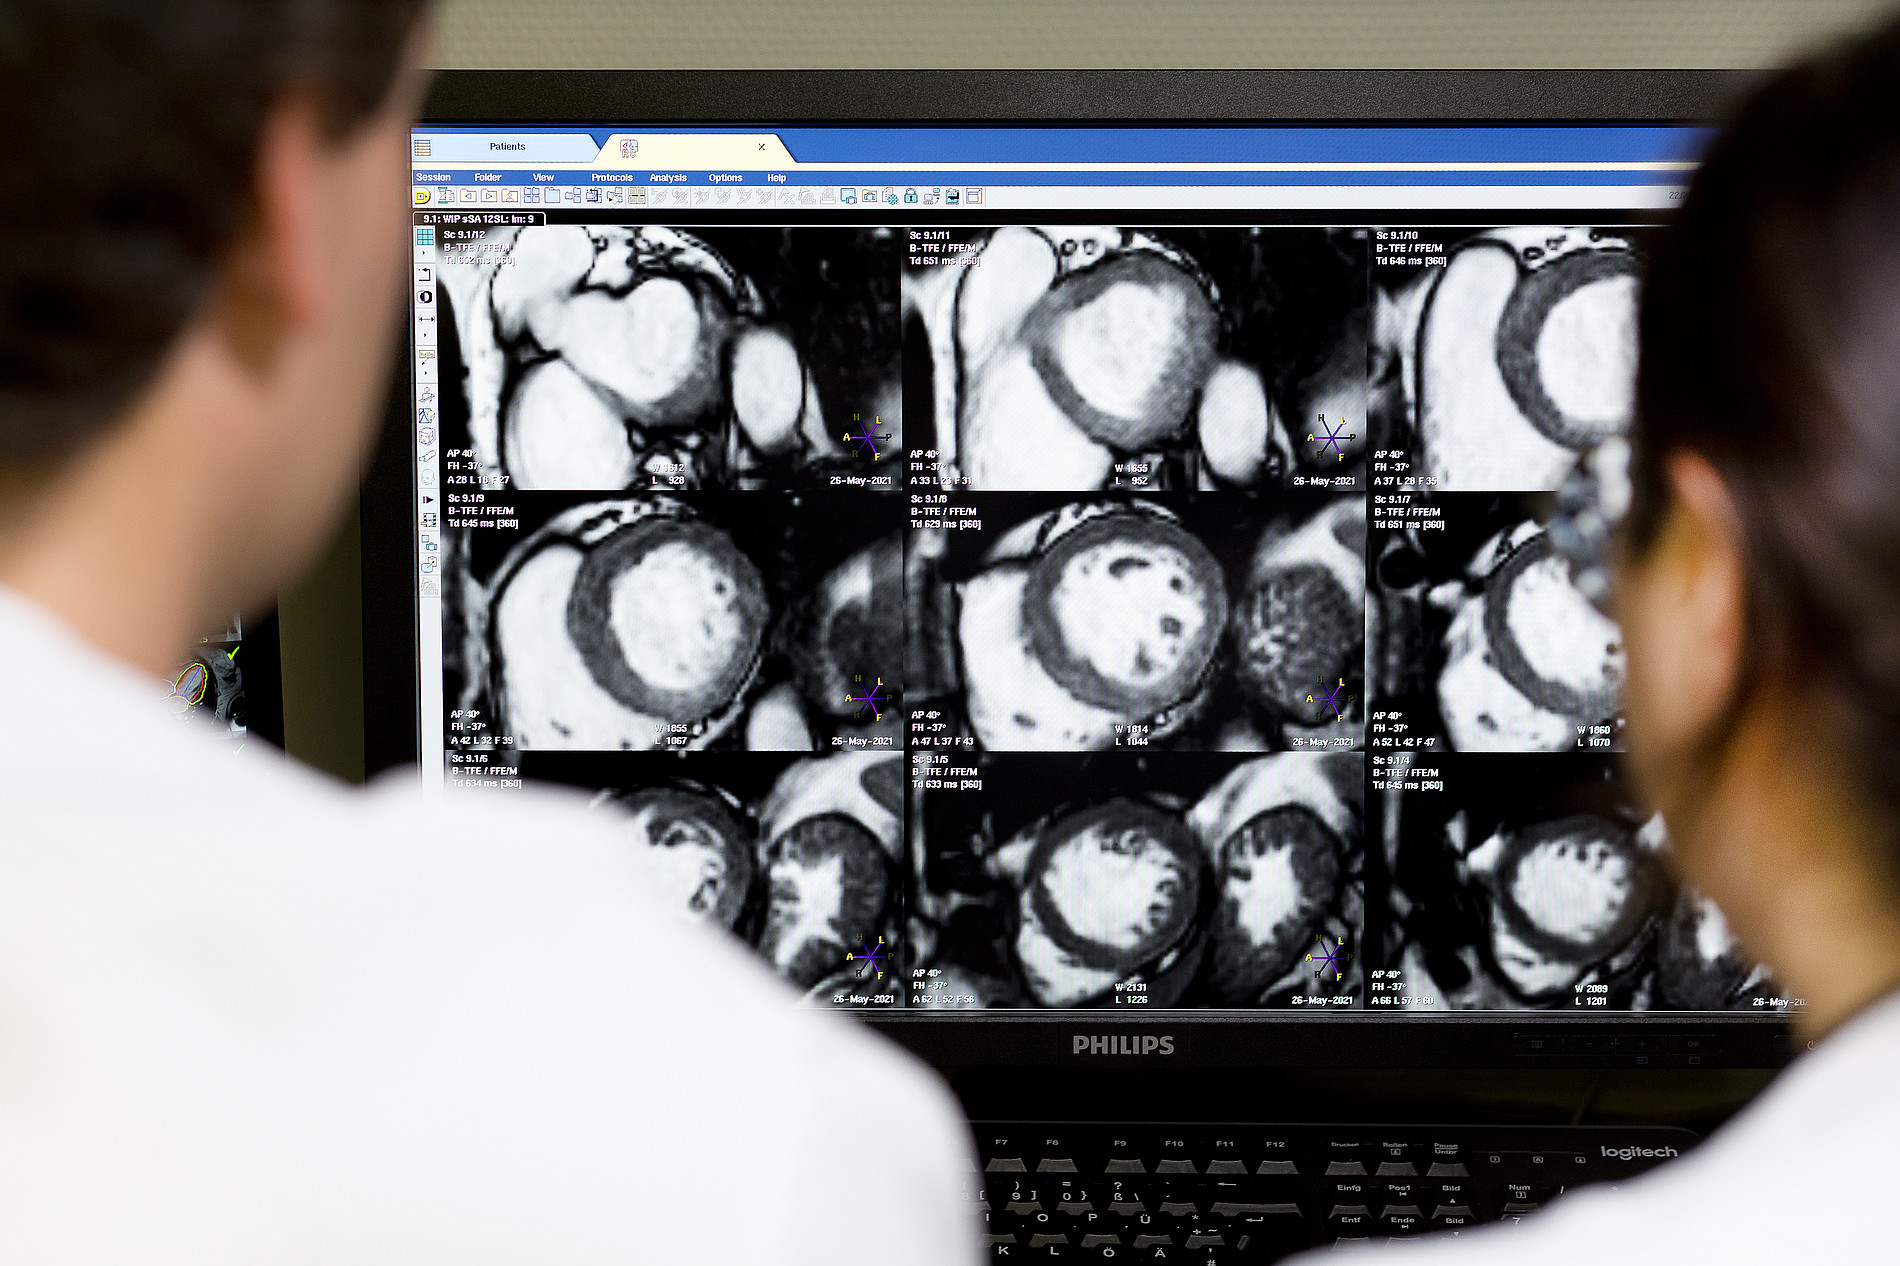

Kardiovaskuläre Magnetresonanztomographie (Cardiovascular Magnetic Resonance, CMR)

Kardiovaskuläre Magnetresonanztomographie (Cardiovascular Magnetic Resonance, CMR) in der Kardiologie am UKD

Die CMR Bildgebung der Kardiologie wurde im Jahre 2011 implementiert und ist neben einer Vielzahl an Forschungsprojekten fester Bestandteil des klinischen Alltags. Mit mehr als 1600 Untersuchungen pro Jahr wird ein großes Spektrum der kardialen Bildgebung abgedeckt. Neben der Diagnostik rund um die koronare Herzerkrankung („Stress-MRT“, nach Herzinfarkt), die mit ca. 40% der Gesamtuntersuchungszahl die häufigste Indikation darstellt, sind vor allem die Diagnostik der entzündlichen (ca. 20%) sowie der nichtentzündlichen (ca. 5%) Kardiomyopathien sowie die prä- und postinterventionelle Klappenevaluation (ca. 5%) Schwerpunkte des CMR. Jedoch werden auch seltene Erkrankungen, wie angeborene komplexe Herzfehler und kardiale Tumore, regelmäßig untersucht.

Die Kardiologie des UKD ist zur CMR-Weiterbildung von der Ärztekammer Nordrhein bevollmächtigt und als Qualifizierungsstädte der Zusatzqualifikation CMR von der DGK zertifiziert. Es besteht eine Vollzeitbesetzung durch einen Arzt mit Akkreditierung. Dadurch werden wir dem hohen Anspruch einer fachlichen Versorgung auf internationalem Niveau gerecht. Die Implementierung des CMRs am UKD als integraler Bestandteil der Kardiologie sowie der hohe Vernetzungsgrad innerhalb der Funktionsabteilungen optimiert Patientenpfade, verkürzt Wartezeiten, und ermöglicht eine umfassende sowie effiziente Diagnosefindung. Stets werden die neuesten Forschungssequenzen der Abteilung getestet und angewendet.

CMR innerhalb der großen 4 Säulen der Kardiologie:

1. Koronare Herzerkrankungen (KHK) z.B. Ischämiediagnostik

2. Strukturelle Herzerkrankungen(SHD) z.B. Vitiendiagnostik

3. Herzinsuffizienz/ Intensiv (CHF) z.B. Mitra Clip

4. Rhythmuserkrankungen